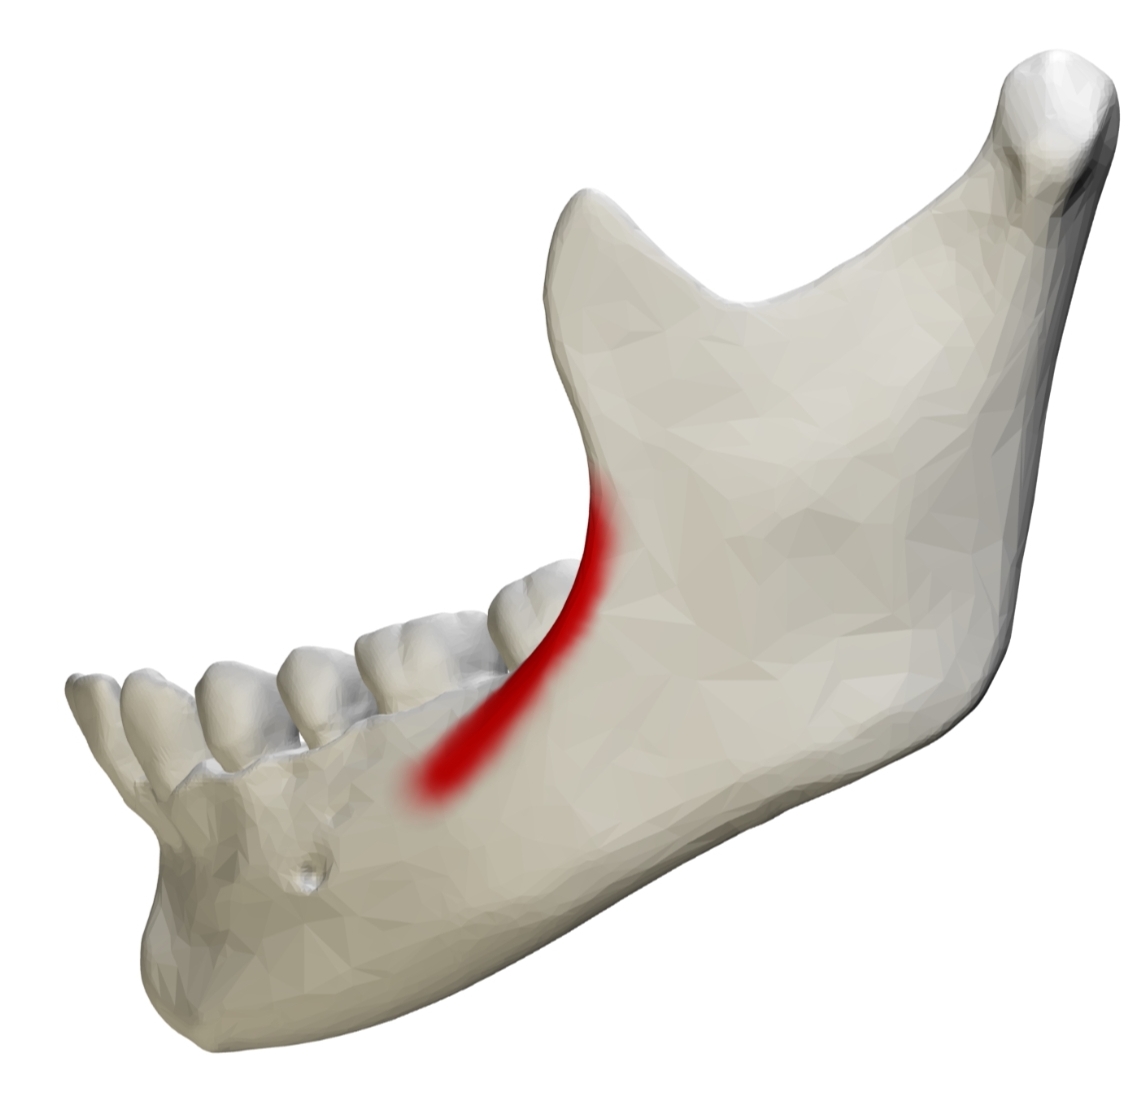

Large ridge of facial; located vertically on ramus

External Oblique Ridge